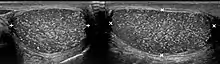

Testicular microlithiasis is an unusual condition diagnosed on testicular ultrasound. It is found in between 1.5 to 5% of normal males, and may be found in up to 20% of individuals with subfertility. It is an asymptomatic, non-progressive disease.

The cause is unknown, but this condition has been associated with testicular cancer in a small group of individuals, cryptorchidism, mumps, infertility and intraepithelial germ cell neoplasia. Classic testicular microlithiasis is defined as five or more echogenic foci per view in either or both testes, and limited testicular microlithiasis defined as one or more echogenic foci that do not satisfy the criteria for classic testicular microlithiasis. In 80% of cases, both testicles are affected.